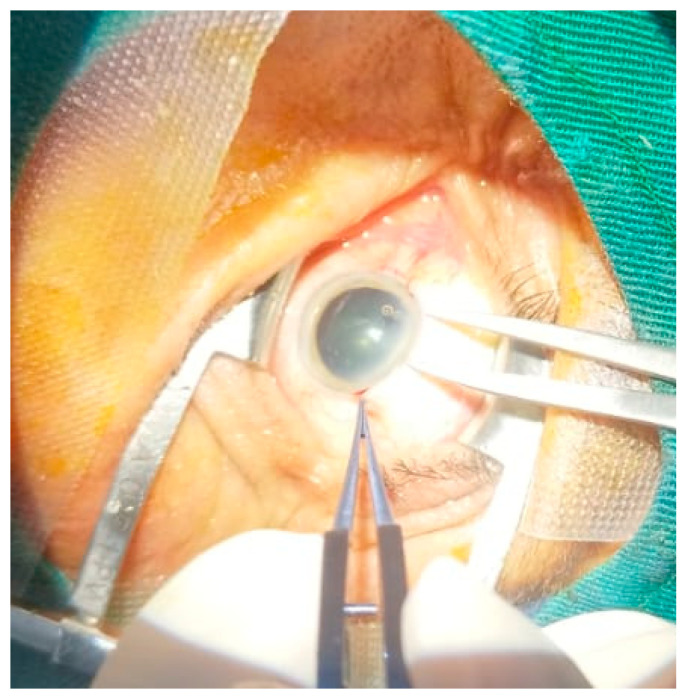

Cataracts remain one of the leading causes of reversible blindness in low- and middle-income countries such as Ecuador. This study assessed the efficacy of Small Incision Cataract Surgery (SICS) and analyzed sociodemographic and clinical factors associated with postoperative visual outcomes. A retrospective multicenter analysis was conducted across six ophthalmology clinics along the Ecuadorian coast between 2023 and 2024, including 558 patients aged 30 years or older. Postoperative visual acuity, measured using the LogMAR scale, improved significantly (mean improvement of 0.525 LogMAR units in the right eye (OD) and 0.489 LogMAR units in the left eye; p < 0.001). Ages between 60 and 69 years were associated with better outcomes in the right eye, while male sex was a protective factor against poor visual acuity in the left eye. Although diabetes mellitus and hypertension were prevalent, neither condition showed a significant association with postoperative visual outcomes. The findings confirm that SICS is a safe, effective, and cost-efficient surgical approach for restoring vision in resource-limited settings, supporting its inclusion in national public health strategies to reduce avoidable blindness in developing countries.